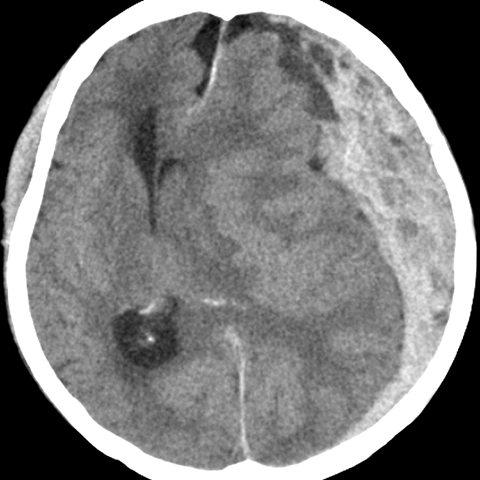

55 year old female presents to the emergency room after a car accident [3 of 4]